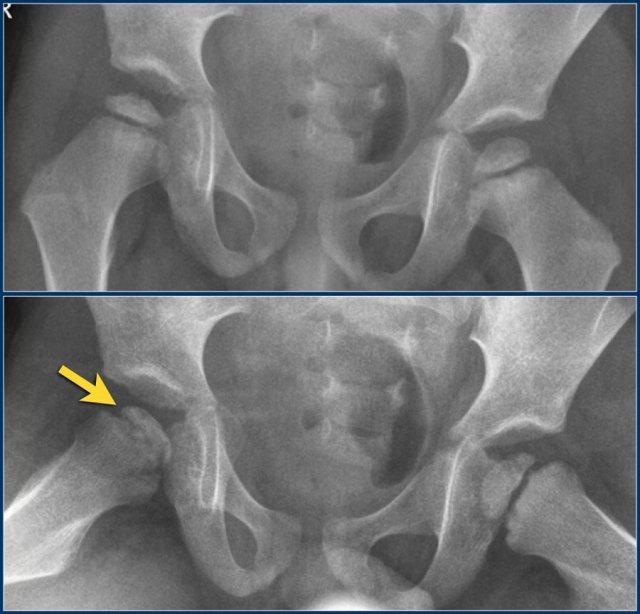

Các hình ảnh cho thấy bệnh Perthes khớp háng phải ở một bé trai năm tuổi.

Các dấu hiệu bao gồm:

- Đầu xương đùi dẹt và xơ cứng.

- Gãy xương dưới sụn, được đánh giá rõ nhất trên tư thế chụp nghiêng kiểu ếch.

Ở giai đoạn sớm của bệnh, phim X-quang có thể âm tính, nhưng MRI sẽ cho thấy phù nề chỏm xương đùi với mất tín hiệu cao của tủy xương trên chuỗi xung T1W.

Đôi khi một đường gãy xương ẩn trên X-quang có thể được phát hiện trên MRI dưới dạng dấu hiệu viền đôi trên chuỗi xung T2W có fatsat.

Tràn dịch khớp có thể hiện diện.

Sụn có thể trở nên phì đại ở bên bị ảnh hưởng.

Các hình ảnh cho thấy bệnh Perthes bên phải ở một bé gái chín tuổi.

Có sự mất tín hiệu cao T1W của tủy mỡ do phù nề và xơ cứng.